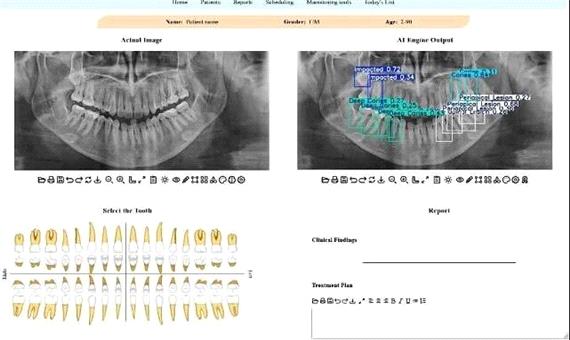

توسعه سامانه هوشمند تحلیل تصاویر دندانپزشکی در دانشگاه تهران

سیاست و بازاریابی - ایسنا / پژوهشگران دانشکدگان فنی دانشگاه تهران، موفق به توسعه یک سامانه هوش مصنوعی شدند که می‌تواند با تحلیل تصاویر پانورامیک دندان، بیماری‌های شایعی مانند پوسیدگی، بیماری‌های لثه و نهفتگی دندان را با سرعت و دقت بالا تشخیص داده و به عنوان دستیار متخصصان، تحولی بزرگ در فرآیند تشخیص و برنامه‌ریزی درمانی ایجاد کند.

به نقل از روابط عمومی دانشگاه تهران، این پژوهش که در قالب یک مقاله از رساله دکترای مهدیه دهقانی و با سرپرستی رضا آقایی‌زاده ظروفی، استاد دانشکده مهندسی برق و کامپیوتر دانشکدگان در یک نشریه بین‌المللی منتشر شده است، نشان می‌دهد که این مدل، قادر است به‌صورت خودکار، محل دقیق ضایعات و ناهنجاری‌ها را در تصویر شناسایی کرده و احتمال درستی تشخیص خود را نیز اعلام کند.

استاد دانشکده مهندسی برق و کامپیوتر دانشگاه تهران با بیان اینکه در این پژوهش جدید محققان تلاش کرده‌اند تا این چالش را با کمک فناوری حل کنند، افزود: برای این منظور یک سامانه تشخیصی مبتنی بر هوش مصنوعی طراحی شده است که این سامانه، معماری پیشرفته شبکه عصبی به نام YOLOv11 است که آموزش آن بر روی یک مجموعه‌داده عمومی انجام شده است. این مدل قادر است به‌صورت خودکار، محل دقیق ضایعات و ناهنجاری‌ها را در تصویر شناسایی کرده و احتمال درستی تشخیص خود را نیز اعلام کند.

ظروفی یکی از نقاط قوت این پژوهش را کاربردی شدن پژوهش در قالب یک اپلیکیشن وب، عنوان کرد و گفت: یکی از نقاط قوت این پژوهش، کاربردی بودن آن است. این مدل در قالب یک اپلیکیشن تحت وب پیاده‌سازی شده تا دندان‌پزشکان و رادیولوژیست‌ها بتوانند به سادگی از آن استفاده کنند. این سامانه با مشخص کردن محل دقیق مشکلات، به پزشک در اولویت‌بندی و تصمیم‌گیری سریع‌تر کمک می‌کند.

وی همچنین افزایش سرعت و اطمینان در تصمیم‌گیری بالینی را از دیگر مزیت‌های استفاده از این سامانه در تشخیص مشکلات دندانپزشکی برشمرد و افزود: به گفته کارشناسان، بهره‌گیری از چنین سامانه‌هایی نه تنها سرعت فرآیند گزارش‌نویسی را افزایش می‌دهد، بلکه به عنوان یک ناظر دوم، می‌تواند با کاهش خطاهای ناشی از خستگی یا حجم بالای کار، دقت تشخیص نهایی را ارتقا دهد و نقش مکملی مؤثر برای متخصصان فک و صورت ایفا کند.

بر اساس نتایج این تحقیق، مدل پیشنهادی در مقایسه با نسخه‌های قبلی، دقت بالاتری در شناسایی و طبقه‌بندی ناهنجاری‌ها از خود نشان داده است.